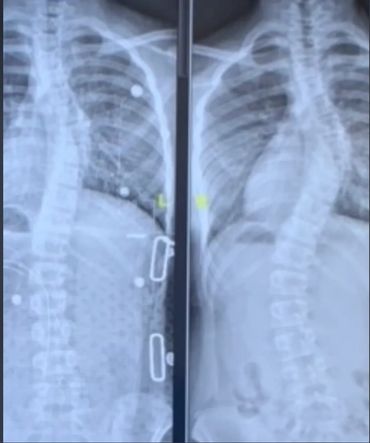

Hi! Above and to the side are some photos of my family, Liz (my brace doctor, who helps tweak and make adjustments to my brace), a couple of my X-rays and me. The side-by-side X-rays show my progress from right to left, The X-ray on the right shows my spine before I got a new brace (since I grew out of my old one) and the picture on the left illustrates my back one month after I got the new brace!